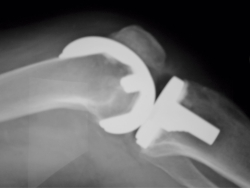

Ante la realización de un corte distal femoral insuficiente, con la consiguiente disminución del espacio en extensión, probablemente aparecerá una limitación de la extensión con una rótula baja (Figura 1). Una altura inadecuada de la interlínea articular produce un desequilibrio ligamentoso a través del arco de movimiento que puede provocar por un lado contractura y por otro inestabilidad. El aumento de la presión del aparato extensor se produce por el desplazamiento anterior del componente femoral, resección insuficiente de las facetas rotulianas y una malrotación de los componentes femoral o tibial. Un sobredimensionamiento del componente femoral compromete la articulación femoropatelar y disminuye el espacio en flexión, con la consecuente limitación de la flexión de la rodilla. Un componente tibial demasiado alto lleva a un aumento de la tensión en flexión y extensión, con lo que habrá la tendencia a producir una contractura en flexión con limitación de la misma. Una pendiente anterior del corte tibial lleva a limitar la flexión.

Figura 1. Rodilla rígida tras artroplastia por “patela baja”.